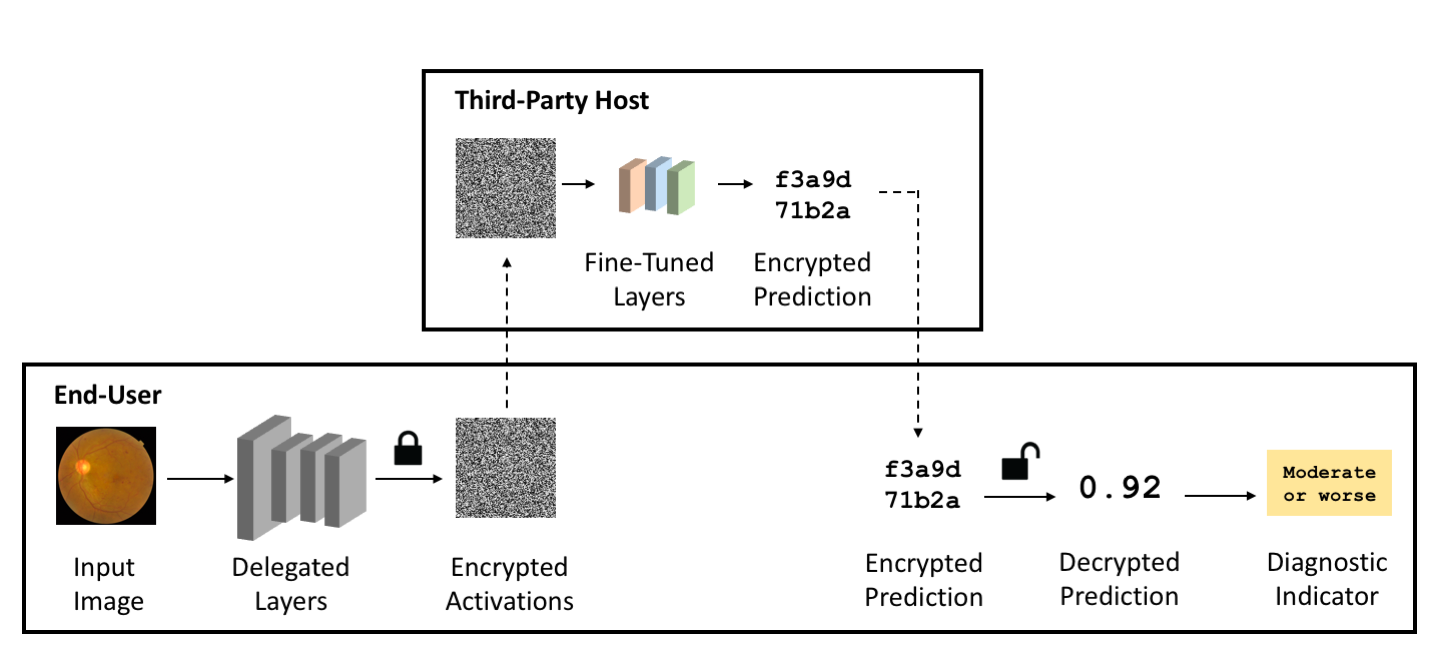

Homomorphic encryption [56] allows a machine learning model to perform calculations over encrypted data. By design, the output prediction is also encrypted, which prevents the input or output from leaking information to the model’s host. As show in Figure 1, the model does not decrypt the data nor is the private key needed [12].

The target use case of our work is inference on a single encrypted image (Figure 1). We believe this approach is more analogous to practical use cases, where the third-party host runs asynchronous inference for individual users. Additionally, [49] suggests that there are very significant drawbacks to batching, including having to select more numerous and restricted NTT points, forcing specific computations away from NTT, and adding large computational cost. Works focusing on accelerating neural networks neglect batching for similar reasons as ours ([59] does not use batching, and [11]. uses batching to compress messages but not to improve throughput). Works that do batch inputs use schemes not very efficient in practice (discussed in [49].) and do not report the batching cost. A thorough performance analysis of batching binary vs scalar messages across different libraries is beyond the scope of our paper but would be a great direction for future work. As such, we do not implement ciphertext batching techniques in this paper, although we find it worth noting that our technique does not preclude the use of batching techniques. [49] introduces the Karatsuba algorithm which supports batching with binary encoding, preserving the benefits from our method.